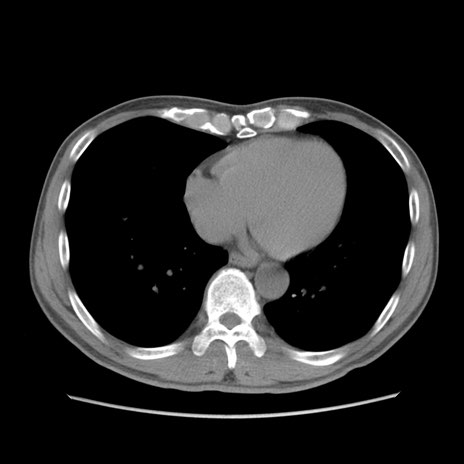

症例56 CT(横断像)

脂肪ウインドウ